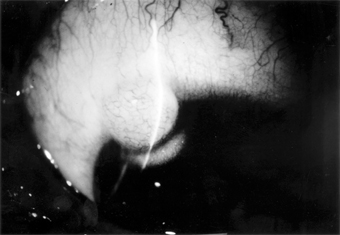

Malignant Melanoma

Malignant melanomas of the conjunctiva are rare. Most arise from areas of primary acquired melanosis; some arise from conjunctival nevi; a few apparently arise de novo from normal conjunctiva. Some are melanotic; others are heavily pigmented (Figure 5-29).

Figure 5-29

Figure 5-29: Conjunctival malignant melanoma.

Many tumors can be locally excised. More radical surgery (eg, exenteration of the orbit) does not usually improve the prognosis. The use of cryotherapy after excision of melanotic tumors may help to prevent recurrences.